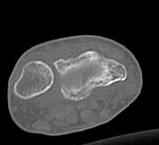

Дальнейшее лечение консервативное. Через 6 недель- гипс снят, назначено ЛФК. Пациентка крайне недовольна. Говорит, что на снимке у нее выступает кость, я ей сломал руку и.т.д. В общем началось. Пациентка прочитала в интернете наверное все, что есть по данной травме. По заключениями рентгенологов и консультанта из КДЦ областной больницы - стояние отломков допустимое. Объективно говоря- снижена высота лучевой кости, диастаз лучелоктевого сочленения, и не сросся шиловидный отросток. однако на РКТ при сравнении с другой стороной- разница незначительная.

2. сравнить снимки РКТ (с двух сторон)- так ли велико укорочение лучевой кости и лучелоктевой диастаз.